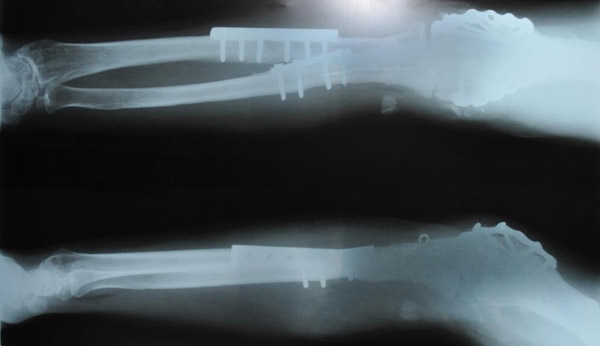

С  2009г  начали  выполнять  протезирование  тазобедренного  сустава  однополюсными  гемипротезами.  Широко  используется  накостный  остеосинтез,  интрамедулярный  остеосинтез  с  блокированием,  чрезкостный остеосинтез  (ЧКОС).

"до операции"

"сама операция"

"после операции"